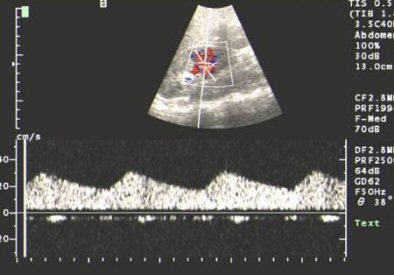

In Moorthy's algorithm, the first step is to screen suspected RAS cases using Doppler ultrasound to look for the following indicators: renal artery stenosis, renal size, evidence of parenchymal damage, mass, and polycystic disease. The drawback with this modality is that the main renal artery is not clearly visualised in as high as 40% of individuals, although intraparenchymal segmental and arcuate arteries can be consistently imaged, Moorthy said.

Quoting from a paper published in Clinical Nephrology, Moorthy said that when arteries are adequately visualised, peak systolic velocity greater than 180-200 cm/sec or a reno-aortic peak systolic velocity ratio greater than 3.5 are considered as reliable criteria to detect significant stenosis. Stenosis in accessory renal arteries may also go undetected. A combined approach of interrogating the main and intrarenal branches has a sensitivity of 96% and a specificity of 98% for detecting RAS compared to angiography (May 2000, Vol. 53:5, pp. 333-343).

Patients with poor outcomes after revascularisation can be identified by ultrasound. For poor outcomes, a renal resistive index of more than 0.8 is taken as the marker.

| US showing tardus-parvus pattern in the arcuate artery. All images courtesy of Dr Srikanth Moorthy, Amrita Institute of Medical Sciences and Research Centre, Cochin. |